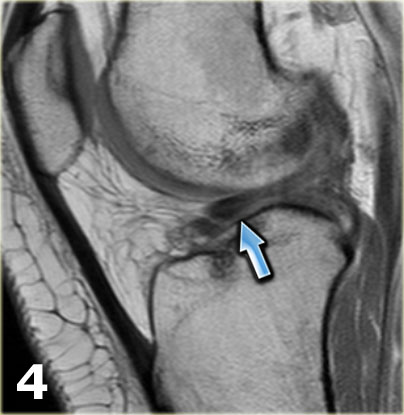

Chúng ta bắt đầu với lát cắt ở giữa của khảo sát.

Lưu ý thân sụn chêm bên có kích thước nhỏ với hình dạng bất thường (mũi tên xanh).

Phần bờ trong bị khuyết được nhìn thấy ngay phía ngoài dây chằng chéo trước (mũi tên đỏ). - Phần sụn chêm bị rách di lệch vào trong, tức là phần quai xách, có thể được theo dõi theo hướng ra sau trong hố gian lồi cầu.